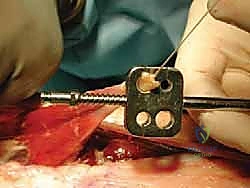

- Calcaneal Tunnel Preparation:

- Measurement: Measure the diameter of the harvested FHL tendon. This dictates the size of our bone tunnel.

- Tunnel Location: A corresponding-sized bone tunnel will be drilled into the posterior tubercle of the calcaneus. This tunnel must be placed directly anterior to the attachment of the distal stump of the Achilles tendon.

- Technique: We'll start by drilling a guide wire, such as a Beath pin, through the calcaneus from posterior to anterior. Confirm appropriate trajectory with fluoroscopy if needed, ensuring it exits anteriorly in a safe location.

- Overdrilling: Once the guide wire is correctly positioned, overdrill it with an appropriately sized cannulated drill bit, matching the FHL tendon diameter. This creates a smooth-walled tunnel for tendon passage.

TECH FIG 4 • D. The FHL tendon diameter is measured, allowing accurate tunnel sizing.

TECH FIG 4 • E. A Beath pin is drilled through the calcaneus immediately anterior to the Achilles tendon insertion.

TECH FIG 4 • F. The Beath pin is overdrilled with an appropriately sized cannulated drill bit so as to facilitate passage of the FHL tendon.